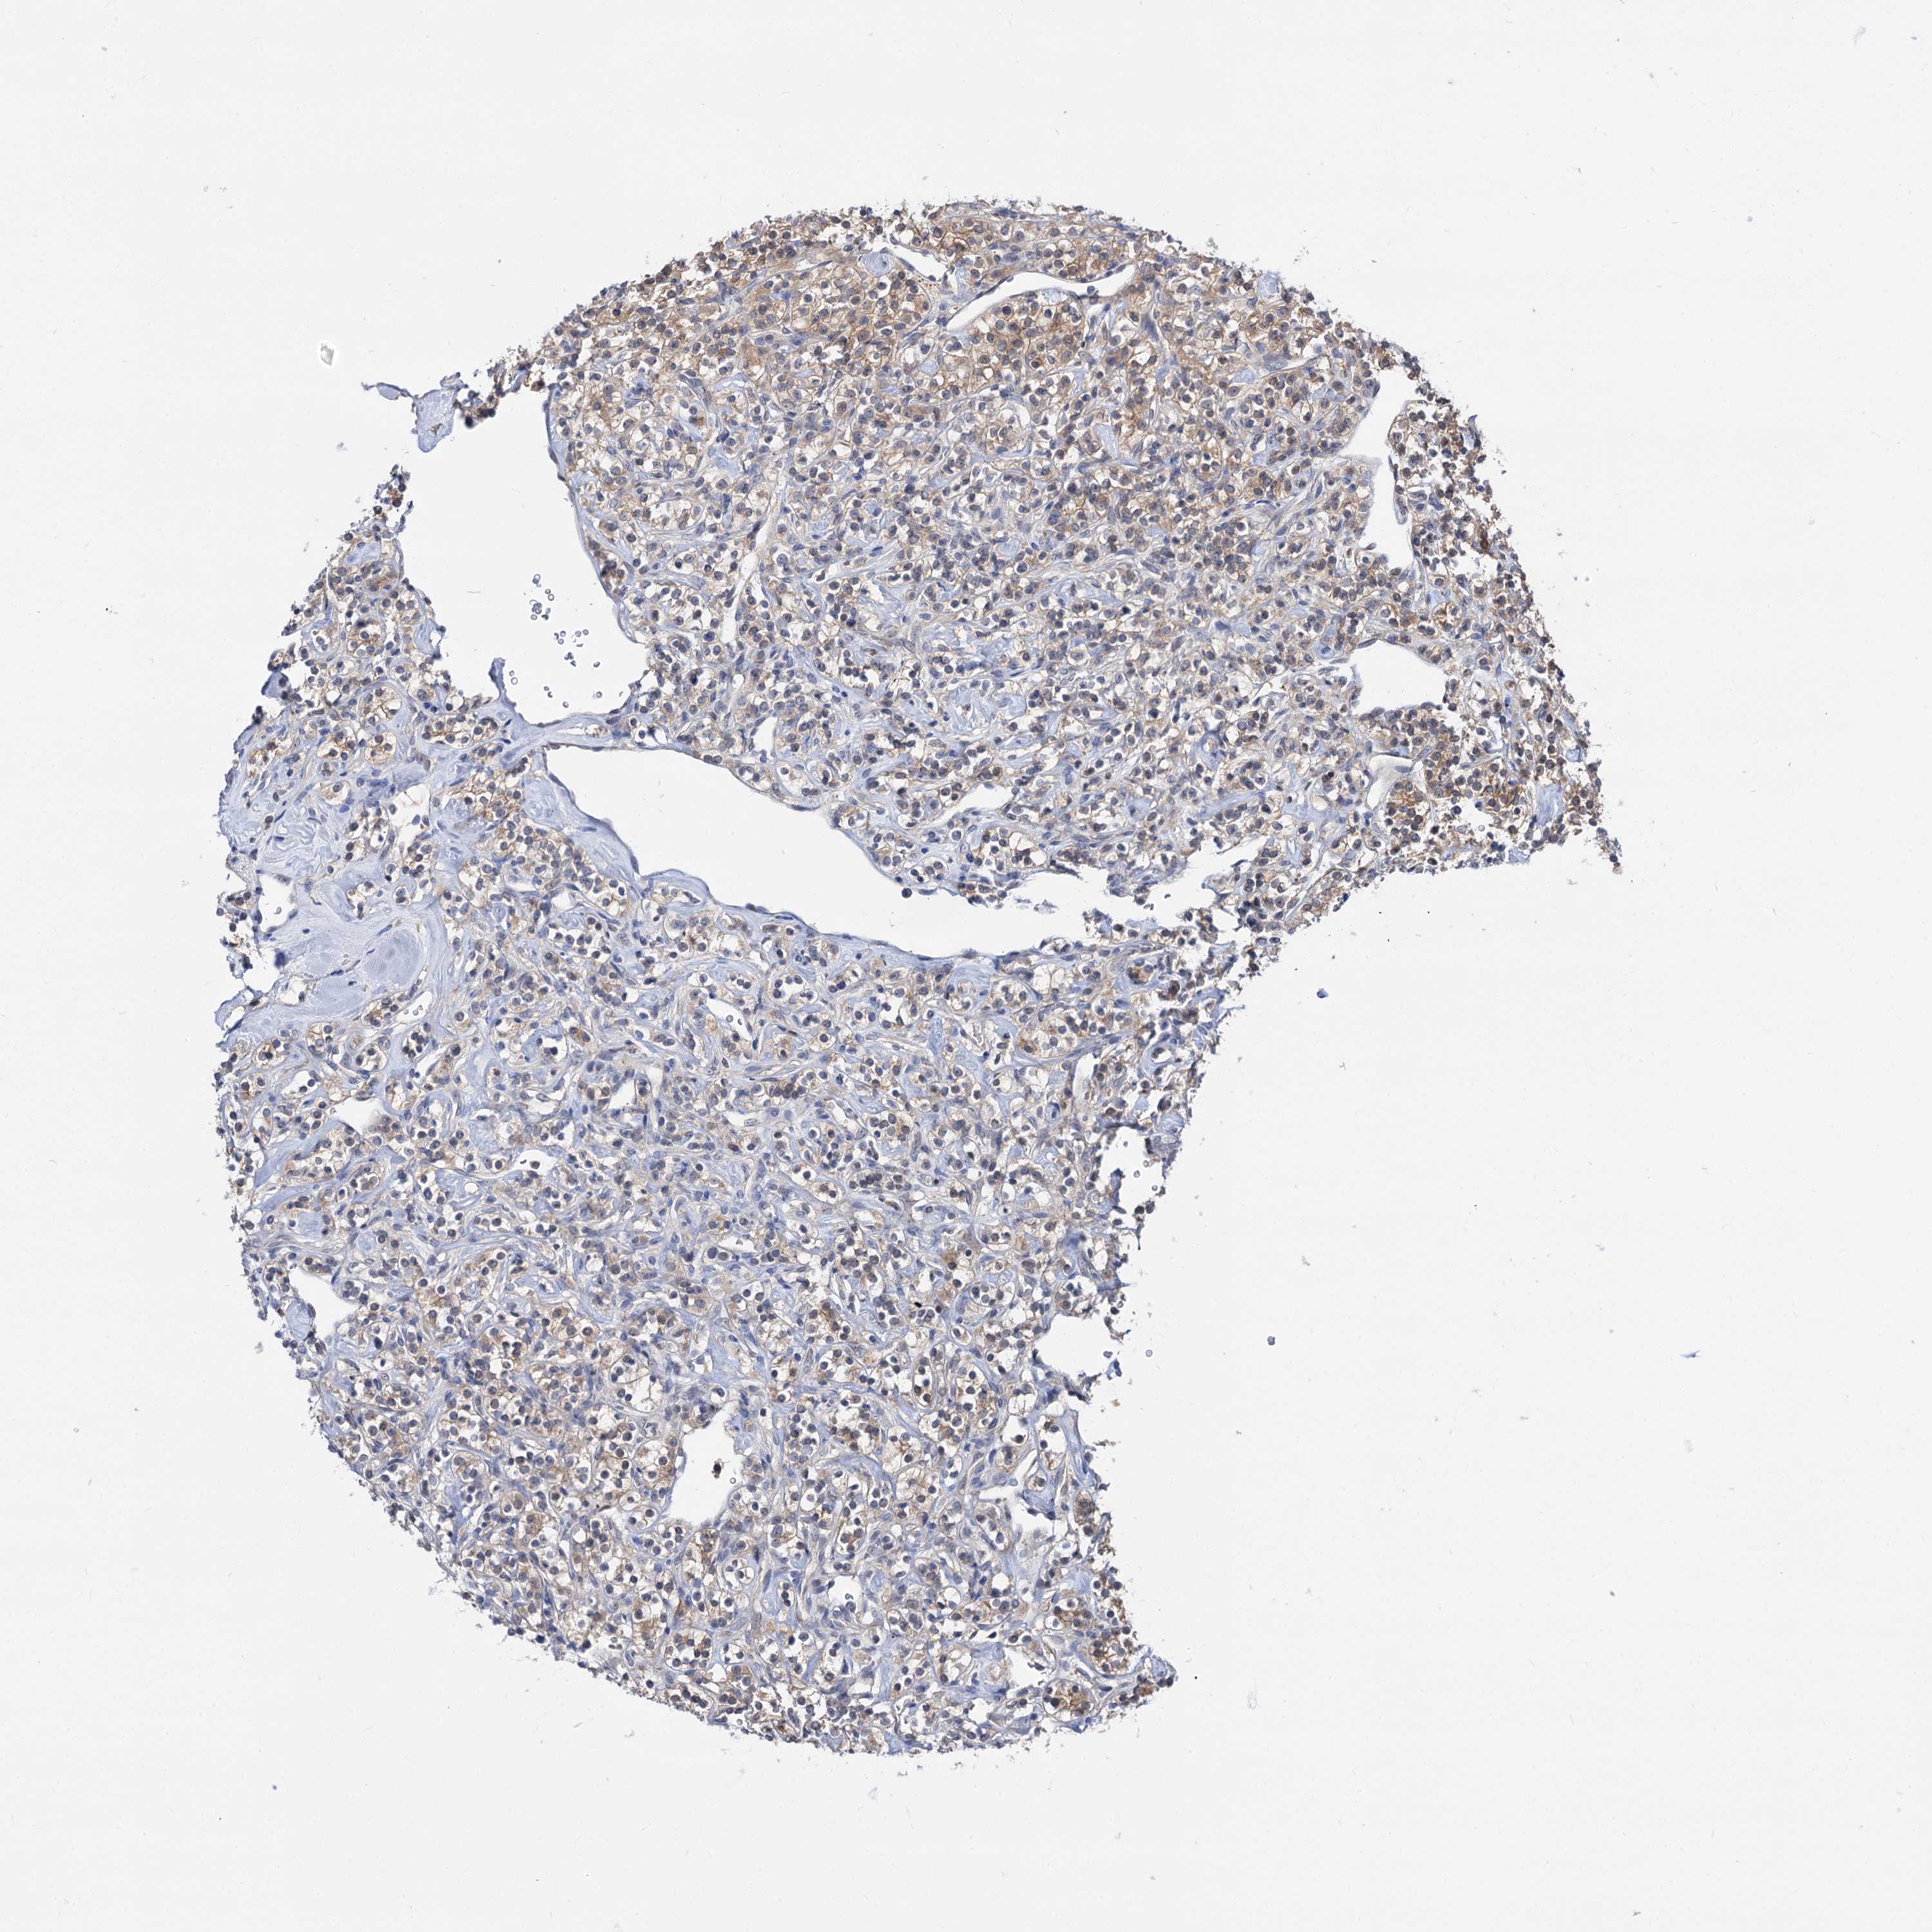

KIDNEY RENAL CLEAR CELL CARCINOMA (VALIDATION) - Interactive survival scatter ploti

The Survival Scatter plot shows the clinical status (i.e. dead or alive) for all individuals in the patient cohort, based on the same data that underlies the corresponding Kaplan-Meier plots. Patients that are alive at last time for follow-up are shown in blue and patients who have died during the study are shown in red.

The x-axis shows the expression levels (FPKM) of the investigated gene in the tumor tissue at the time of diagnosis. The y-axis shows the follow-up time after diagnosis (years). Both axes are complimented with kernel density curves demonstrating the data density over the axes. The top density plot shows the expression levels (FPKM) distribution among dead (red) and alive patients (blue). The right density plot shows the data density of the survived years of dead patients with high and low expression levels respectively, stratified using the cutoff indicated by the vertical dashed line through the Survival Scatter plot. This cutoff is automatically defined based on the FPKM cutoff that minimizes the p-score. The cutoff can be changed by dragging the vertical line or by entering a cutoff value in the square labeled "Current cut-off".

Under the Survival Scatter plot the p-score landscape (black curve; left axis) is shown together with dead median separation (red curve; right axis). Dead median separation is the difference in median mRNA expression between patients who have died with high and low expression, respectively. It is calculated as follows: median FPKM expression of dead patients with high expression - median FPKM expression of dead patients with low expression. This is intended to aid the user in visually exploring custom cutoffs and the associated p-scores and dead median separation.

Individual patient data is displayed and can be filtered by clicking on one or more of the category buttons on the top of the page. Categories describing expression level and patient information include: high, low, alive, dead, female, male and tumor stages. The scale of the x-axis can be toggled between linear and log-scale by clicking on the "x log" button. Mouse-over function shows TCGA ID, patient information and mRNA expression (FPKM) for each patient.

& Survival analysisi

Kaplan-Meier plots summarize results from analysis of correlation between mRNA expression level and patient survival. Patients were divided based on level of expression into one of the two groups "low" (under cut off) or "high" (over cut off). X-axis shows time for survival (years) and y-axis shows the probability of survival, where 1.0 corresponds to 100 percent.

NEK10 is not prognostic in Kidney Renal Clear Cell Carcinoma (validation)

Best expression cut offi

Based on the FPKM value of each gene, patients were classified into two groups and association between prognosis (survival) and gene expression (FPKM) was examined. The best expression cut-off refers the FPKM value that yields maximal difference with regard to survival between the two groups at the lowest log-rank P-value. Best expression cut-off was selected based on survival analysis .

When clicking on this number, the vertical dashed line indicating cut-off, the interactive survival plot, and the Kaplan-Meier curve will be adjusted to show results based on the best expression cut-off.

: 1.6

P scorei

Log-rank P value for Kaplan-Meier plot showing results from analysis of correlation between mRNA expression level and patient survival.

N/A

TCGA RNA samplesi

RNA-seq data is reported as average FPKM (number Fragments Per Kilobase of exon per Million reads), generated by the The Cancer Genome Atlas (TCGA) .

Normal distribution across the dataset is visualized with box plots, shown as median and 25th and 75th percentiles. Points are displayed as outliers if they are above or below 1.5 times the interquartile range. FPKM values of the individual samples are presented next to the box plot.

Average pTPM 1.2

Number of samples 100